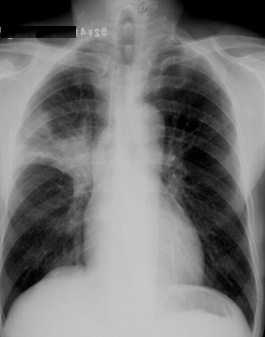

滿肺可見“滿天星”,根據公式診斷肺轉移瘤

斑片狀陰影位于雙肺尖,根據公式診斷浸潤性肺結核